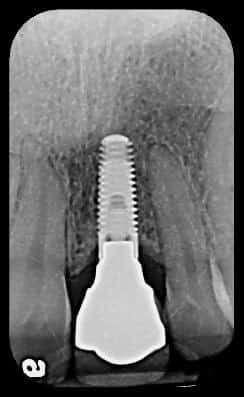

Missing front tooth requiring implant replacement

At Elite Prosthetic Dentistry, we understand the distress caused by a missing front tooth. Renowned prosthodontist Dr. Gerald Marlin will replace the missing tooth with a “simply radiant, simply natural” crown seated on an optimal abutment installed on a perfectly positioned dental implant. Dr. Marlin and his team are highly respected for their problem-solving approach that consists of meticulous planning and flawless execution.

During your consultation with Dr. Marlin, he will consider all the options and assure you that your front teeth can be replaced. Our primary front tooth replacement treatment is to install a crown seated on an optimal abutment and dental implant.

Dr. Marlin has surgically placed and restored over 3,400 dental implants. Additionally, his crowns last up to 35 years, which far exceeds the national average (five to ten years).